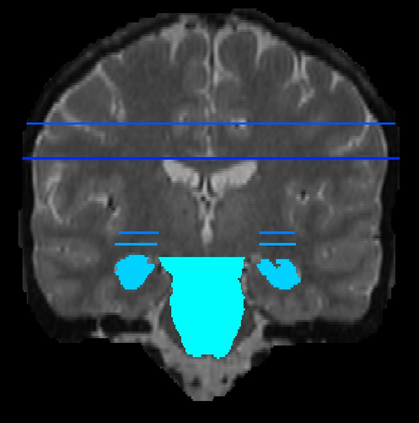

Imaging markers of cerebral small vessel disease provide valuable information on brain health, but their manual assessment is time-consuming and hampered by substantial intra- and interrater variability. Automated rating may benefit biomedical research, as well as clinical assessment, but diagnostic reliability of existing algorithms is unknown. Here, we present the results of the \textit{VAscular Lesions DetectiOn and Segmentation} (\textit{Where is VALDO?}) challenge that was run as a satellite event at the international conference on Medical Image Computing and Computer Aided Intervention (MICCAI) 2021. This challenge aimed to promote the development of methods for automated detection and segmentation of small and sparse imaging markers of cerebral small vessel disease, namely enlarged perivascular spaces (EPVS) (Task 1), cerebral microbleeds (Task 2) and lacunes of presumed vascular origin (Task 3) while leveraging weak and noisy labels. Overall, 12 teams participated in the challenge proposing solutions for one or more tasks (4 for Task 1 - EPVS, 9 for Task 2 - Microbleeds and 6 for Task 3 - Lacunes). Multi-cohort data was used in both training and evaluation. Results showed a large variability in performance both across teams and across tasks, with promising results notably for Task 1 - EPVS and Task 2 - Microbleeds and not practically useful results yet for Task 3 - Lacunes. It also highlighted the performance inconsistency across cases that may deter use at an individual level, while still proving useful at a population level.